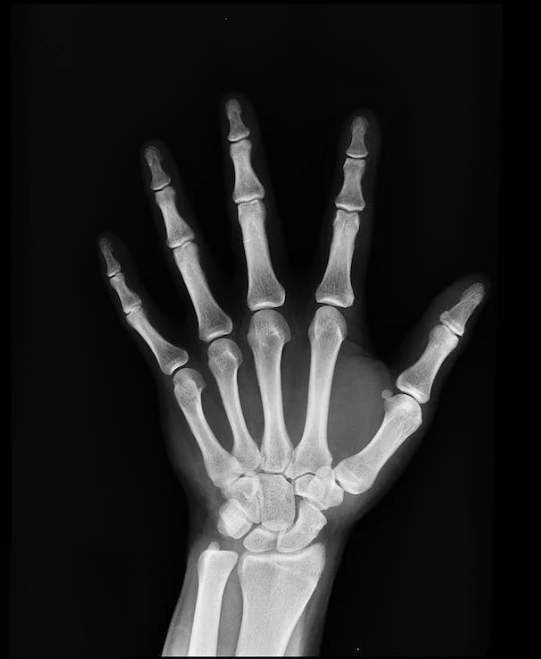

관절연골 손상 진단은 의사와 상담 및 신체 검사를 포함합니다. 이미지 검사, 특히 X-선 및 MRI 검사는 손상 정도를 확인하는 데 중요한 역할을 합니다. 관절연골 손상의 치료법은 손상의 정도와 종류에 따라 다를 수 있으며, 치료법에는 약물 치료, 물리치료, 관절경 수술, 또는 종종 관절 대체 수술이 포함됩니다. 이러한 치료법은 통증 완화와 관절 기능 회복을 위해 사용됩니다.